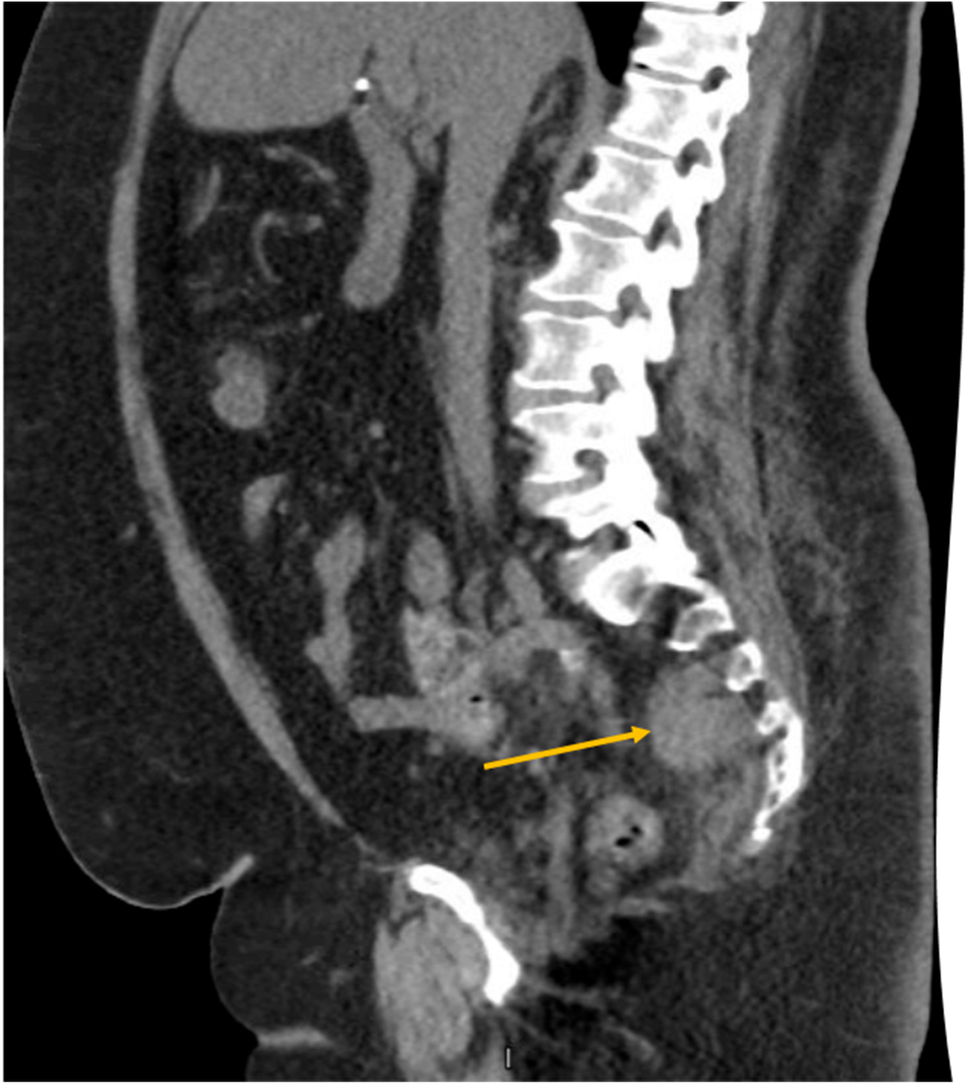

Fig. 1

Computed tomography showing the right-sided piriformis hematoma (yellow circle) contrasting with the normal side (green circle)